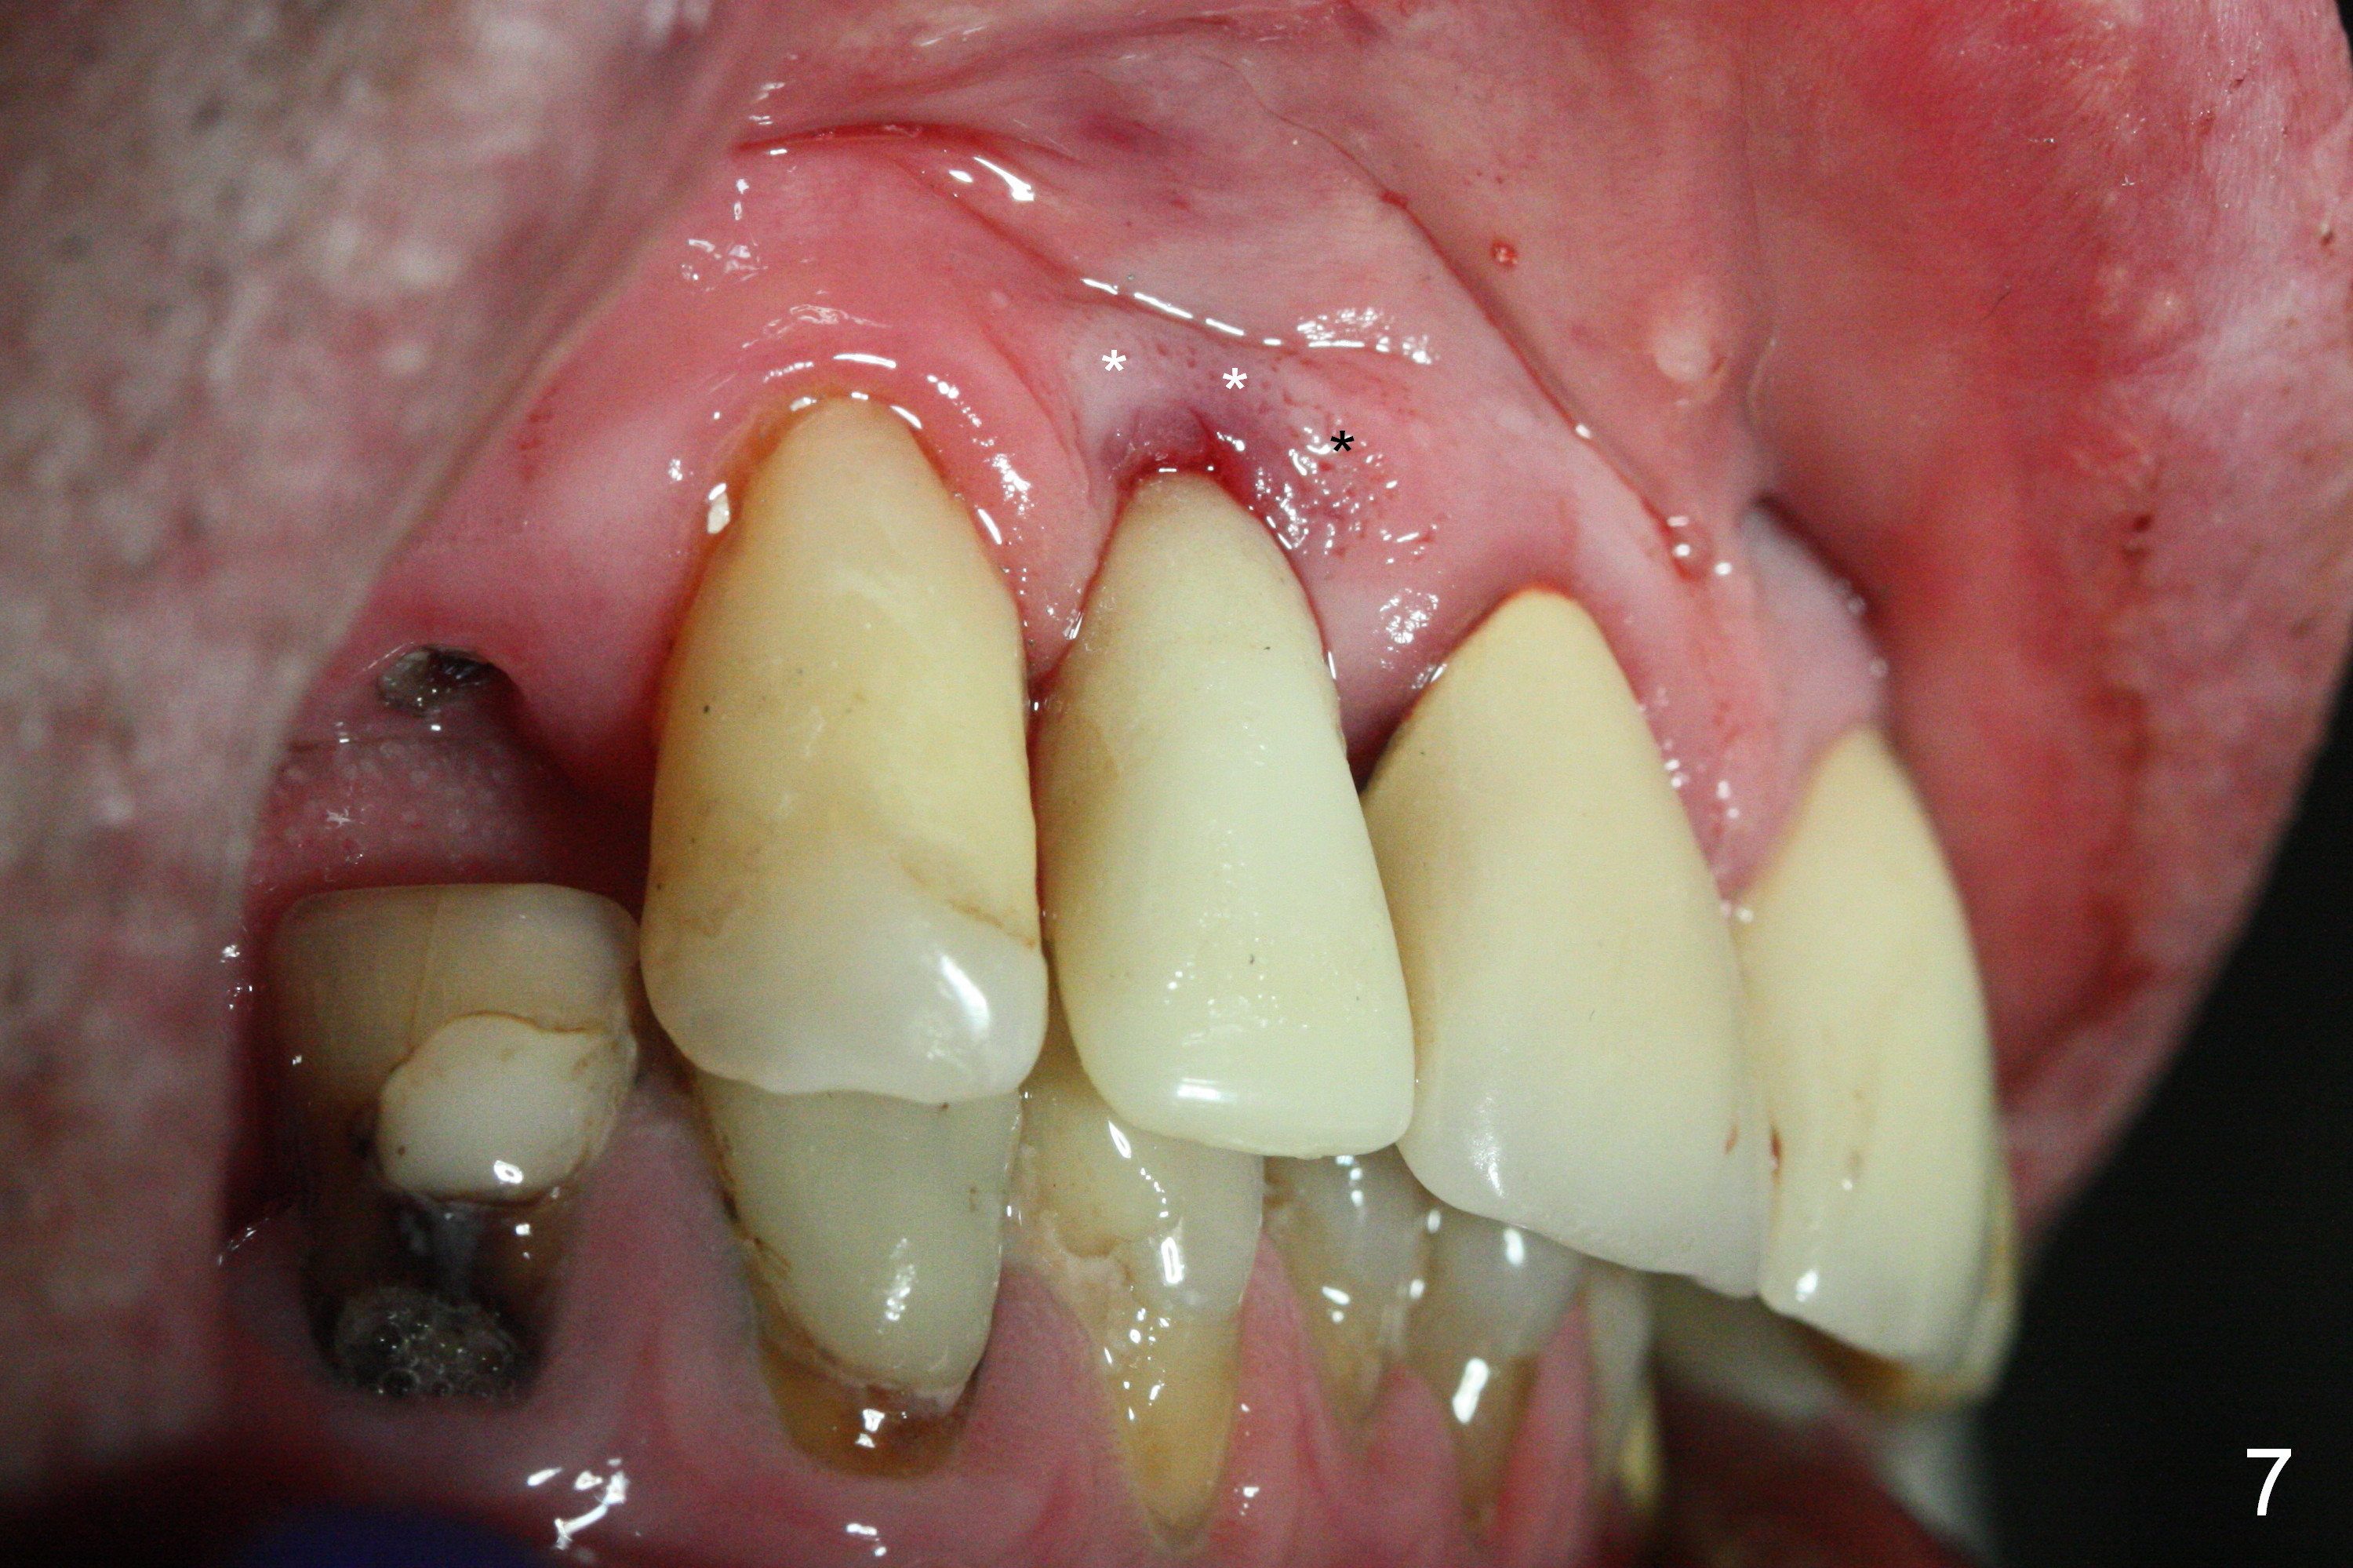

The residual root at #7 is fairly well exposed with buccal gingival recession (Fig.1). The implant placement is flapless (Fig.2-7). What is not shown is that the 3.8x13 mm implant is buccally subcrestally placed (Fig.3). After 1st round of bone graft buccal to the implant, a 4.5x5(5) mm abutment is immediately placed and prepared (Fig.4,5). An immediate provisional is placed after 2nd round of bone graft subgingivally buccally (Fig.6,7). Note the bulging gingiva (*), as compared to that in Fig.4,5. The long implant is chosen because of anterior deep bite (Fig.4) and lack of posterior support (Fig.7).